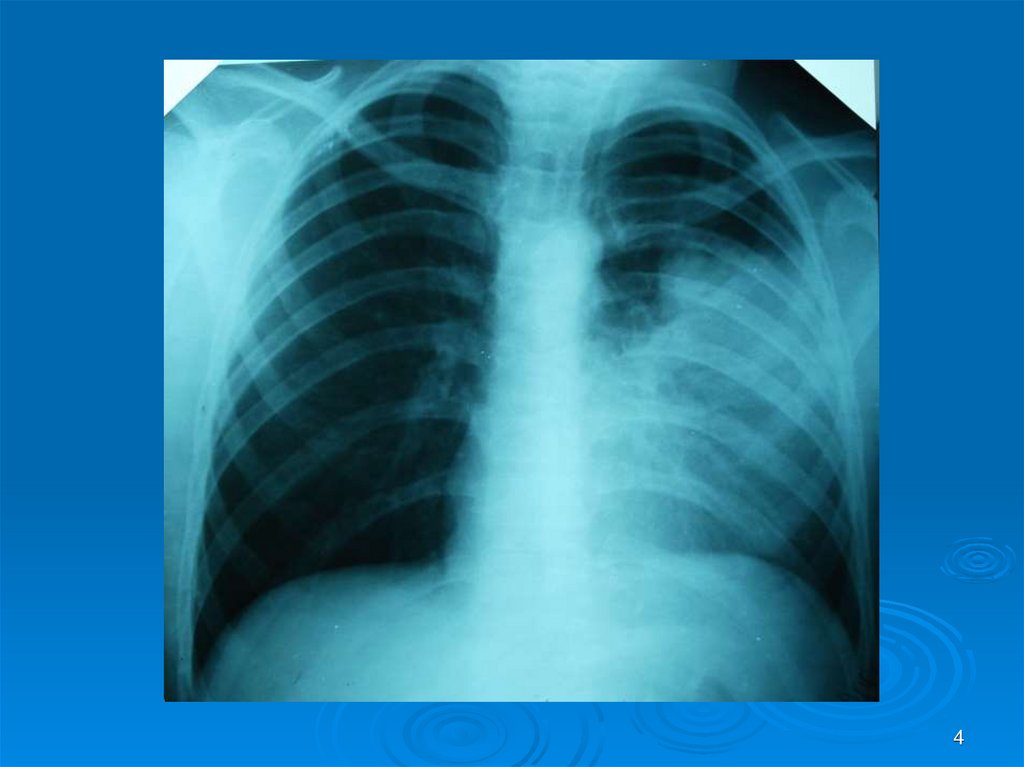

4.

4